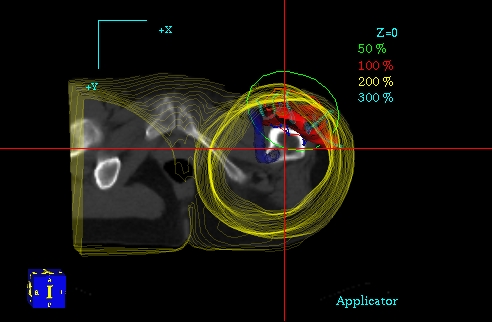

Planowanie 3D PLATO - przekrój czołowy, widoczny CTV, rozkład izodoz